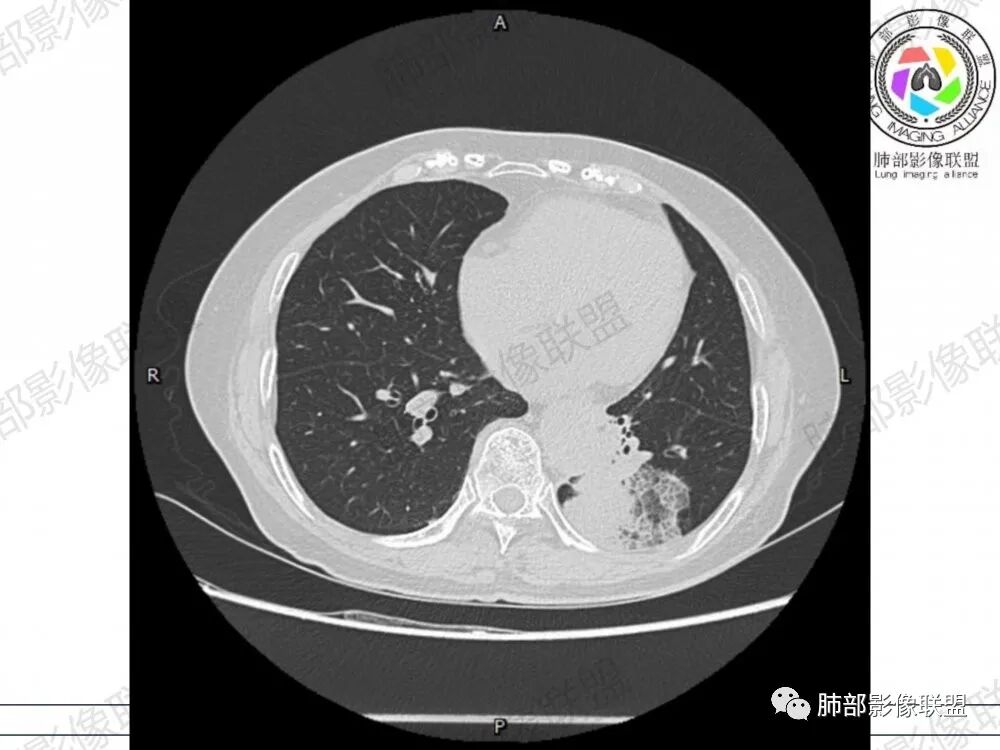

空腔+铺路石征+边界清楚GGO+病灶内血管局部扭曲+强化不均匀+病史长,指向腺癌,特别是粘液腺癌

晨读:左肺下叶胸膜下实性高密度影,部分伴有网格样增厚,内部可见小空泡,壁光滑,周围伴有磨玻璃影,边界清,近端可见支气管穿行,远端支气管堵塞,胸膜下脂肪间隙可见,病变整体收缩,部分有彭隆,增强后可见血管穿行,强化尚均匀。

左肺下叶实变及磨玻璃影,宽基底与胸膜相远,磨玻璃边界清晰,边缘膨隆,病变内近端支气管堵塞,不均匀强化,可见血管影,考虑腺癌,鉴别结核

胸CT:左下叶胸膜下大片斑片影,长轴沿胸膜分布,实变、GGO混杂,磨玻璃边界清晰,粘液密度,小叶内间隔增厚,支气管进入后堵塞(枯枝),增强轻中度强化,血管造影征。常规考虑:肺腺癌?淋巴瘤?鉴别不典型病原体感染。

周围GGO,呈碎石路征,边界清楚

2、影像表现:无肺气肿背景,病变定位于左肺下叶背内侧基底段,病灶呈不规则团块影,靠近胸膜侧,其内密度不均匀,内见空洞、实变及磨玻璃影,磨玻璃影呈碎石路征,边界清楚,实性肿块边界膨隆,其内见空洞。空洞周围比较实。病灶较大的支气管通畅,细小的支气管成“枯枝征”。无胸膜增厚及胸膜腔积液,增强扫描呈中度强化,见血管造影征。